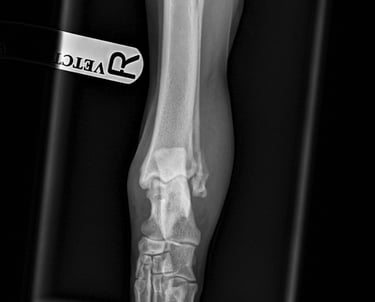

Case 2 - Buddy

Lateral malleolus fracture - Golden retriever, 2y male